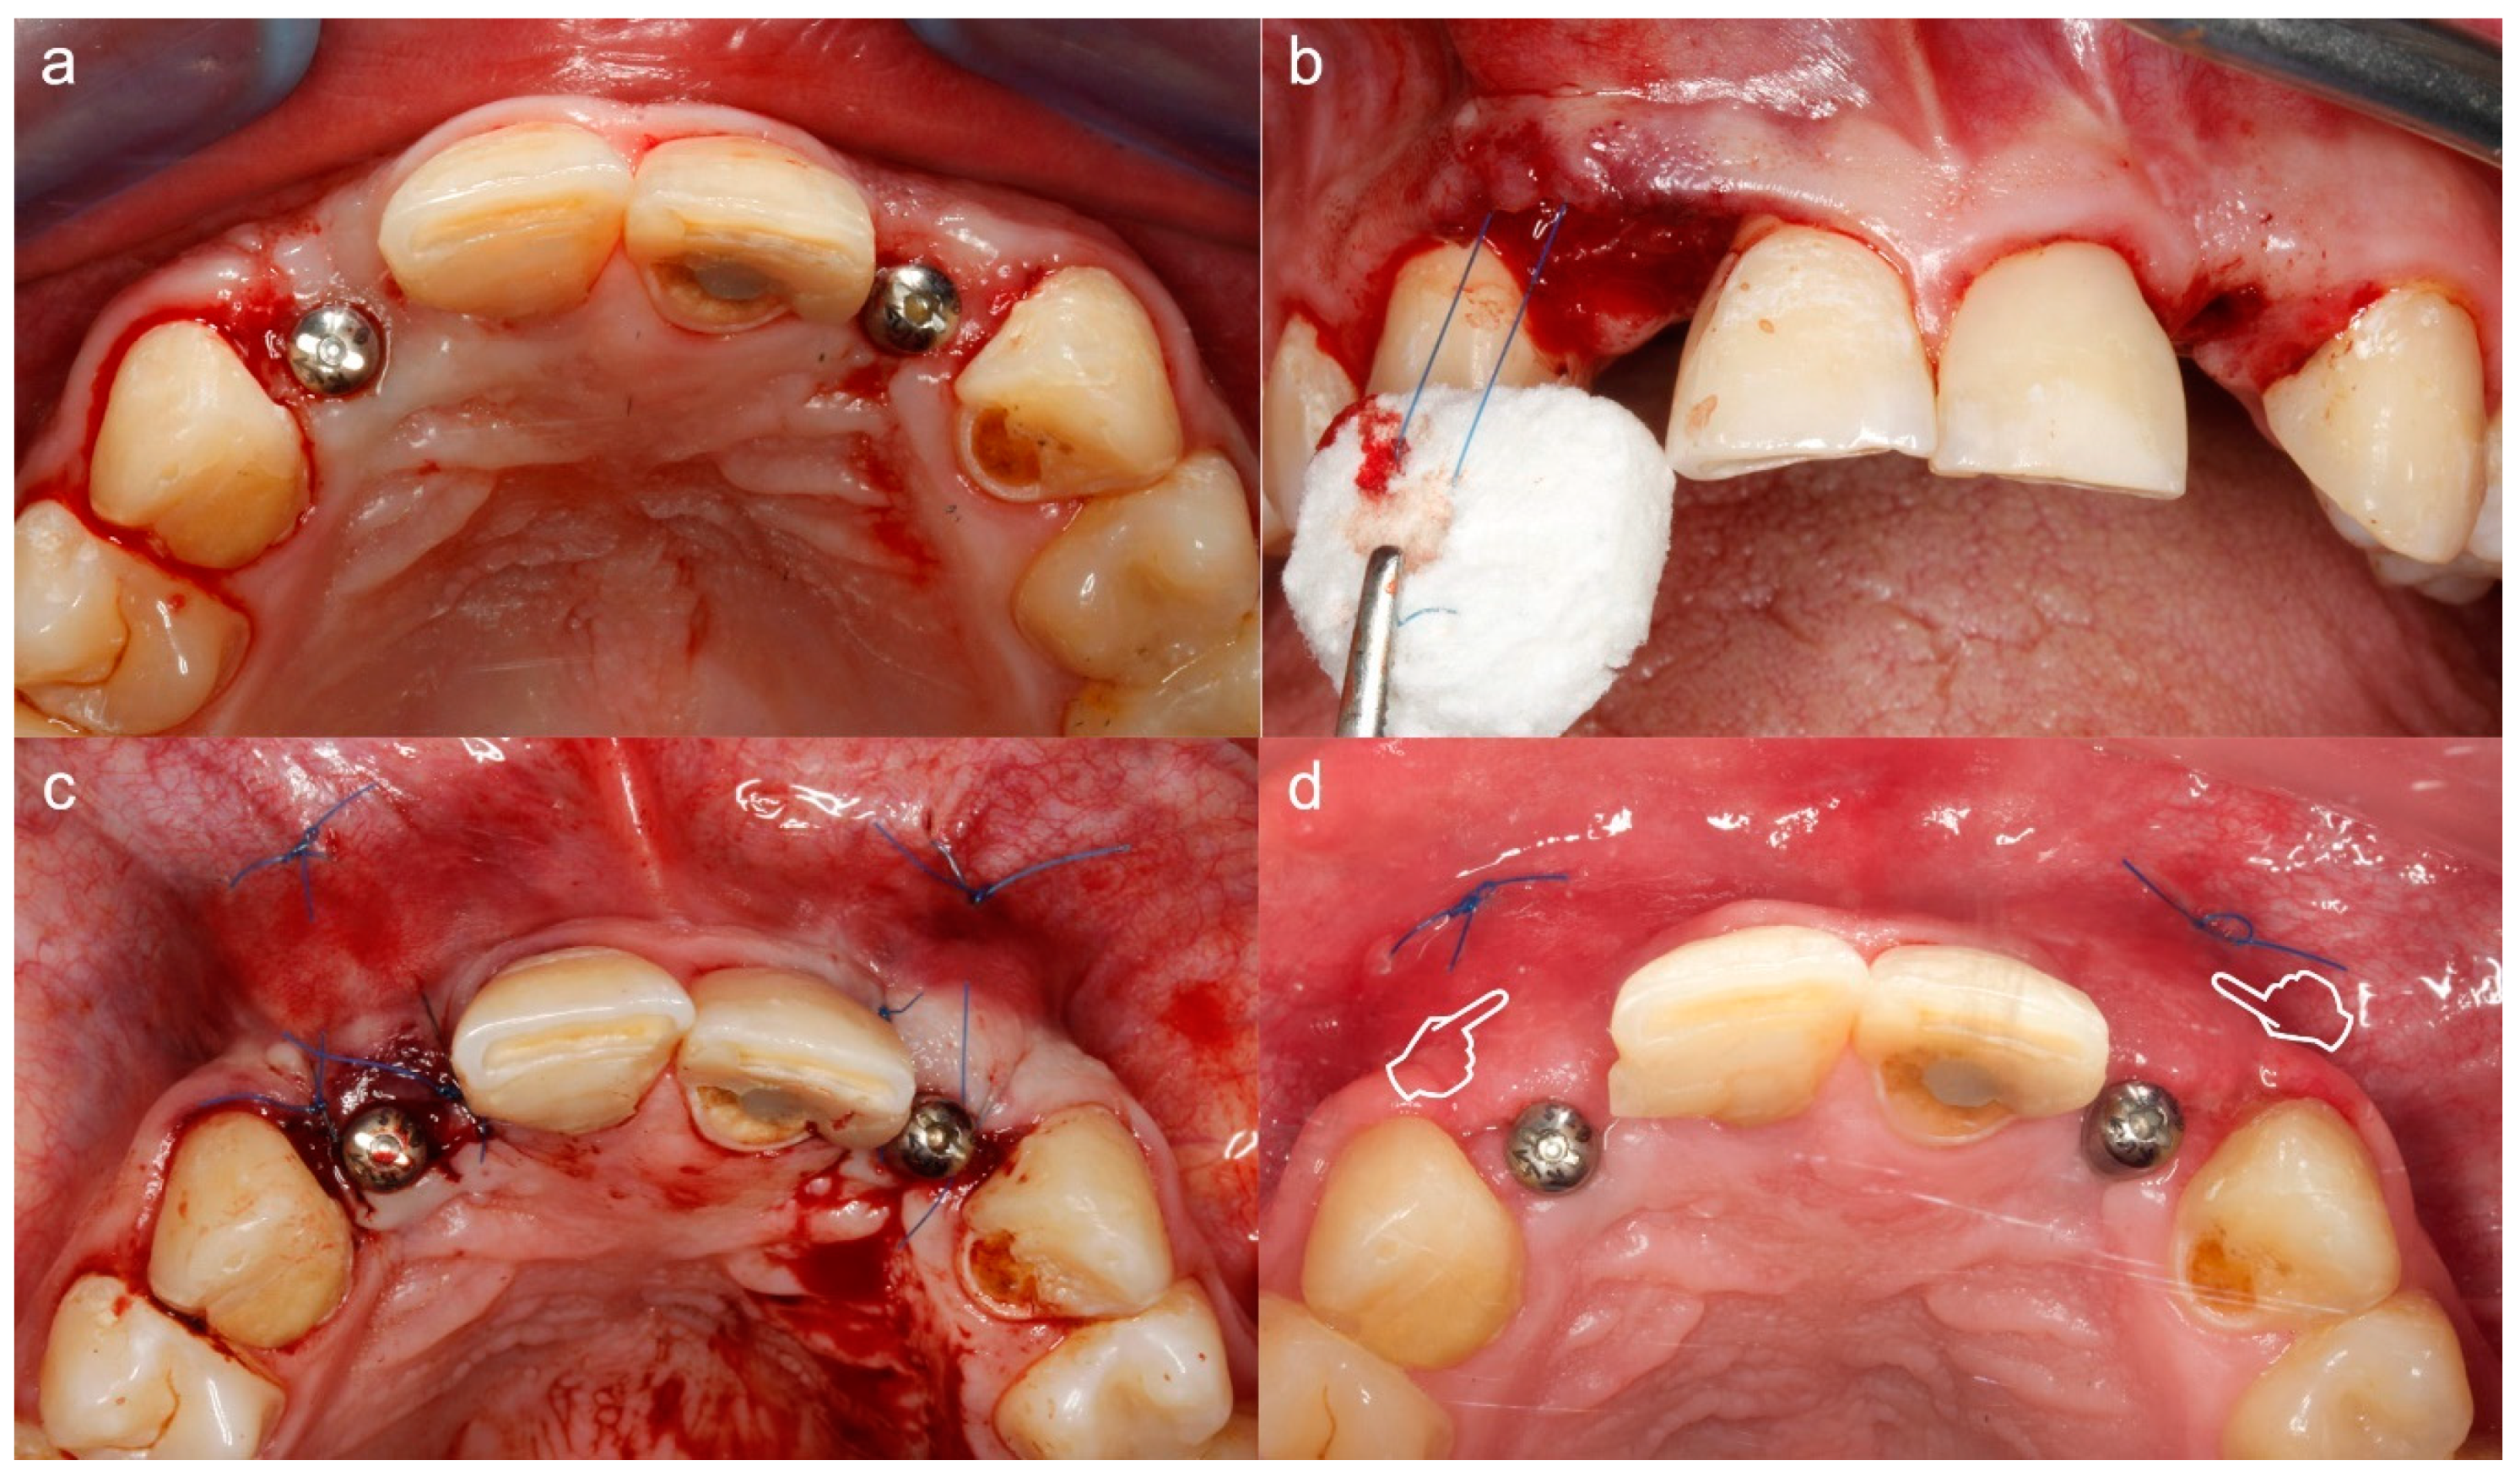

1.2. Periodontal Plastic Surgery and Its Applicability. Autogenous Soft Tissue Graft